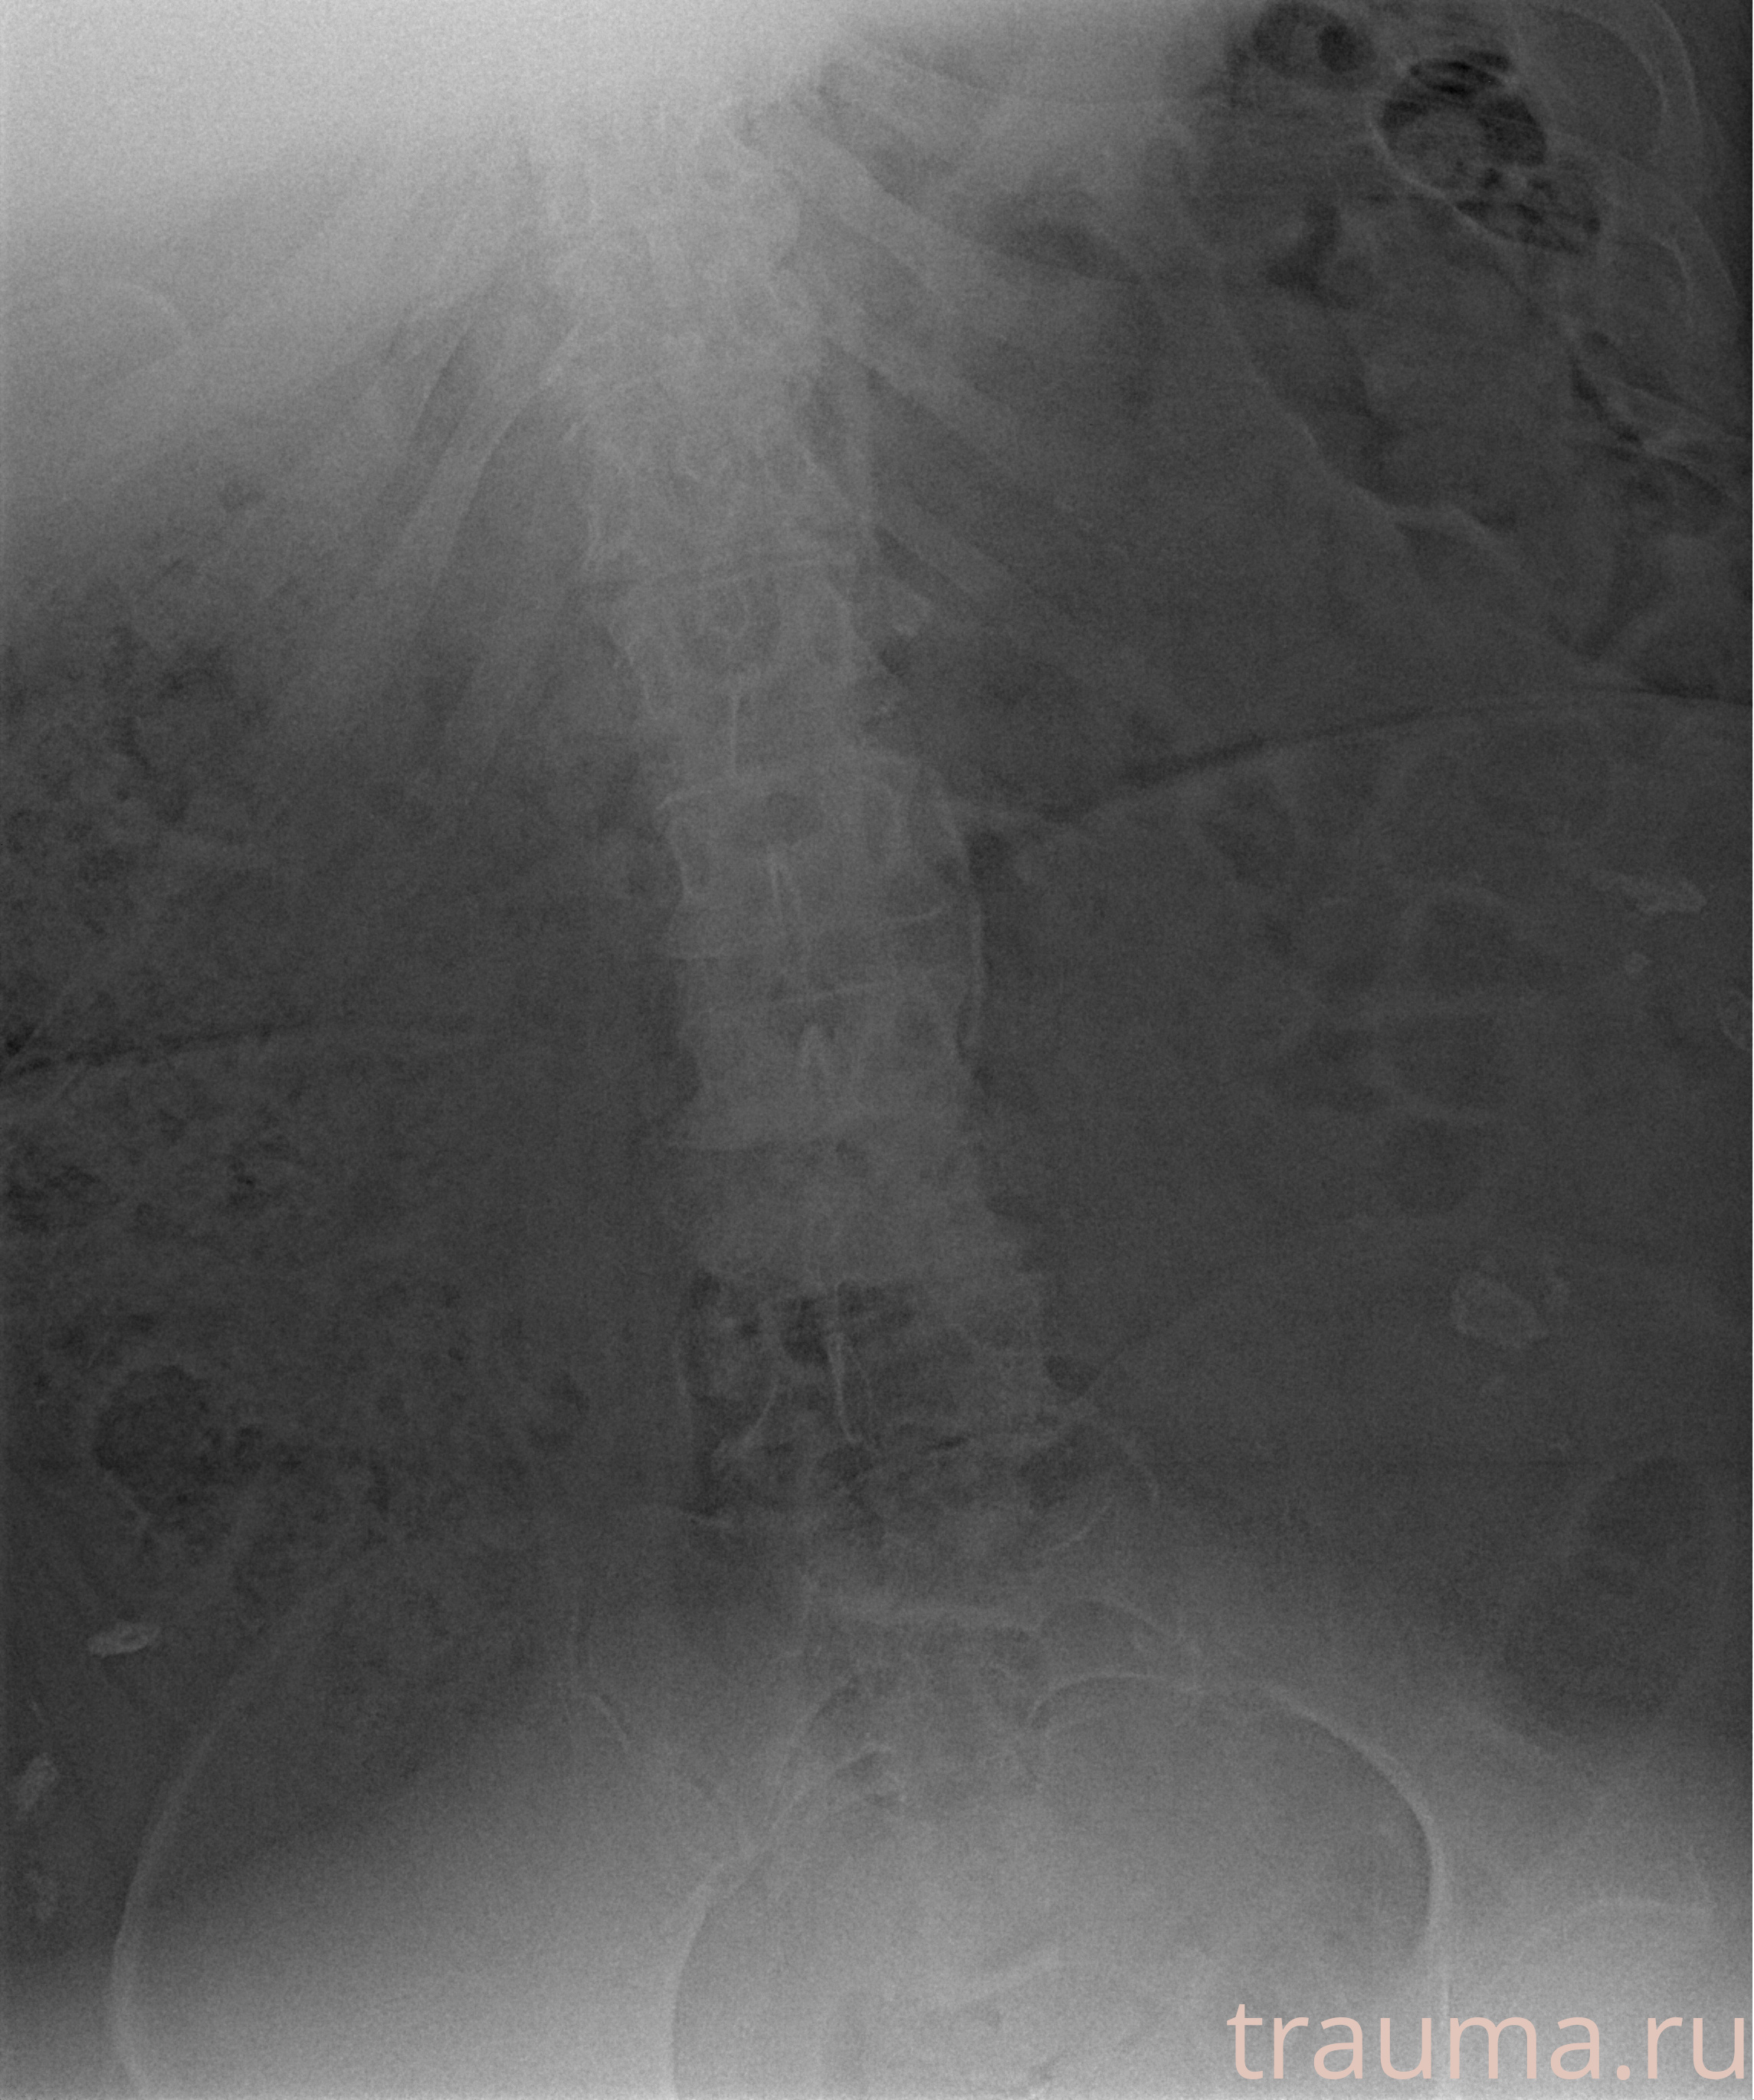

Рентгенограммы

Рентген на дому: по вашему адресу приезжает врач-рентгенолог, травматолог-ортопед с мобильным рентгеновским аппаратом, проводит диагностику травмы или заболевания, делает необходимые рентгенограммы, дает рекомендации по дальнейшему лечению. Получить качественные снимки в домашних условиях возможно благодаря уникальной методике, разработанной МосРентген Центром для института  Склифосовского